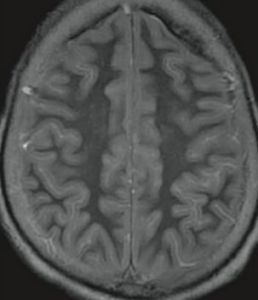

此外,損傷的部位還和局部的血管分布和血管的狀態有關。在發生缺血(氧)時,動脈血管的遠心端供血區域最易發生灌流不足。大腦分別由來自頸內動脈的大腦前動脈、大腦中動脈和來自椎動脈的大腦後動脈供血。其中大腦前動脈供應大腦半球的內側面和大腦凸面的額葉、頂葉近矢狀縫寬約1~1.5cm的區域。大腦中動脈則供應基底核、紋狀體、大腦凸面的大部區域。而大腦後動脈則供應顳葉的底部和枕葉。這樣在3支血管的供應區之間存在一個C形分布的血供邊緣帶,該帶位於大腦凸面,與矢狀縫相平行,且旁開矢狀縫1~1.5cm(圖16-19)。一旦發生缺血性腦病,該區域則最易受累。然而並非每例缺血性腦病病灶都呈C型,病灶的形狀還受局部血管管徑的影響,如果某支血管管徑相對較小,或局部動脈粥樣硬化,則其供血區較易受累。

③邊緣帶梗死(圖16-20)。梗死的範圍與血壓下降的程度和持續的時間有關,如血壓持續下降,則梗死區自遠心端向次遠心端擴大,稱為向心性發展(cardiopetaldevelopment),即C形梗死區向其兩側擴大,並自大腦頂部向顱底發展。大腦缺血性腦病邊緣帶梗死的極端情況是全大腦的梗死,但腦幹的各核團由於對缺血(氧)的敏感性較低仍可存活。患者靠呼吸器以維持生命,但意識喪失,成為植物人。如何處置這樣的病人則成為目前醫學倫理學和醫療實踐的難題。一旦這種病人死亡,其大腦乃成為由腦膜包裹,穢暗無結構的壞死組織,稱為呼吸器腦。